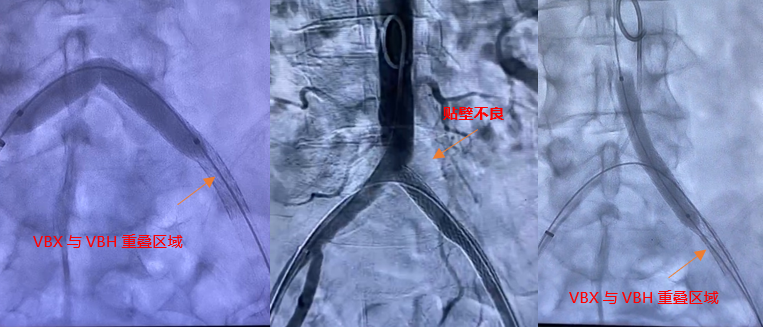

术前造影显示左髂总动脉起始部闭塞,支撑导管辅助翻山成功后,用4X150mm,6X150mm球囊分别做预扩。

(术前造影及4x150mm球囊预扩)

(6x150mm球囊预扩)

预扩后造影显示管腔打开。导入8F长鞘,通过长鞘输送并植入6X100mm 的VIABAHN 支架。继续通过8F长鞘导入VBX 支架,VBX支架近端定位在髂总动脉开口处,远端重叠在VIABAHN 支架内25mm左右。通过长鞘造影判断VBX支架位置后开始释放支架。根据产品外包装提示,当压力泵压力在6atm时,VBX 支架直径为7.1mm,此时支架会完全展开。故第一次加压6atm,支架顺利展开后排空并回撤球囊。调整球囊位置避开支架重叠区,在髂总动脉开口处再次给球囊加压到11atm,观察到支架直径随球囊的增大发生了扩张。根据产品信息提示此时已到达目标直径8mm。撤出球囊后在腹主动脉做整体造影,髂动脉开通良好。但发现VBX 支架近端与左侧腹主动脉分叉处贴壁不完全,判断是由于球囊后扩张是翻山的形式,使支架跟随了球囊的形态导致,故左侧股动脉入路上8mm直径的球囊在VBX开口处进行贴壁性后扩。支架形态被成功纠正,贴壁良好。

释放6x100mm VIABAHN 支架

导入VBX 支架

6atm压力释放

释放VBX支架,11atm的压力

8mm*6cm P3球囊